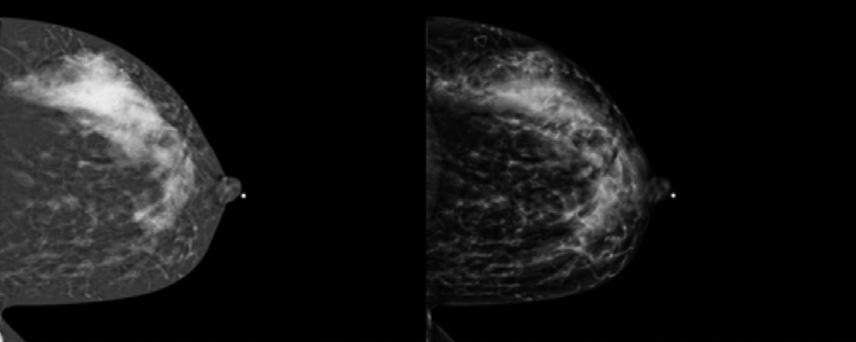

Tout savoir 45 sur l’angio-mammographie

Comprendre cette technique et son application concrète en milieu clinique